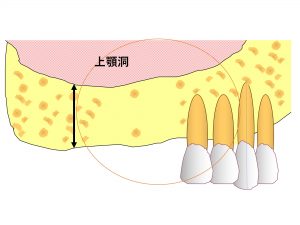

歯周病を放置したり、

歯の根が割れたりしていた場合(歯根破折)、

感染により顎の骨が溶けてしまいます。

以下のようになることもあります。

こうなるとインプラントを行うのに適切な状態とは言えなくなります。

そこで下がった上顎洞を上に押し上げる治療を行うのです。